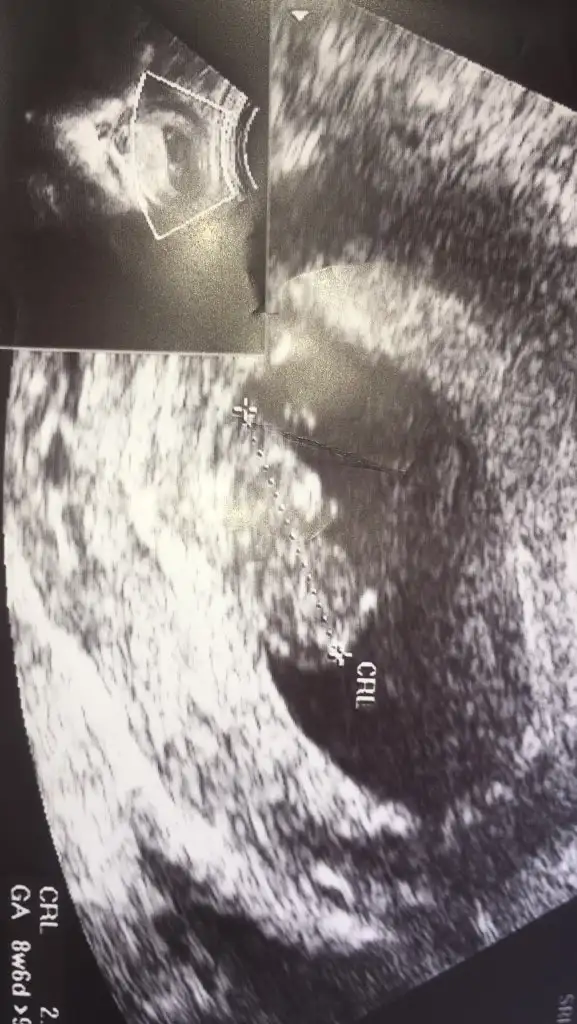

Merhabalar bana da yorum yapar mısınız🤗 6. Ve 7. Hafta karindan ultrason fotolarimizi ekliyorum

• 20201218_121405.webp

20201218_121405.webp

12,2 KB · Görüntüleme: 323